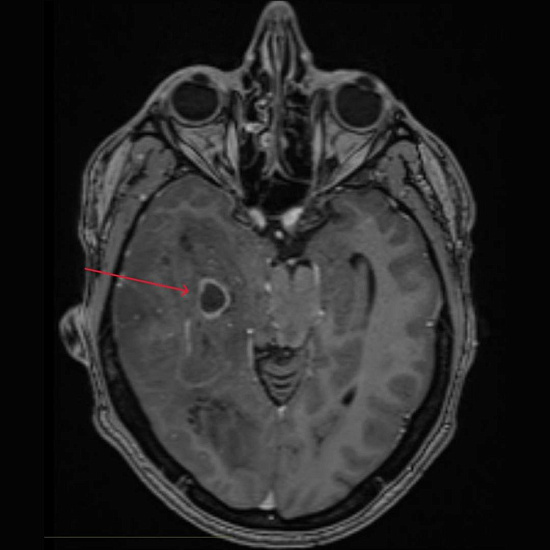

При проведении МРТ головного мозга выявлена опухоль правой височно-теменной области с переходом на островок, вовлечением базальных ядер справа и мозолистого тела с выраженным перифокальным отеком с дислокацией срединных структур мозга влево, компрессией правых бокового и третьего желудочков, среднего мозга.

При введении контрастного препарата визуализировался участок интенсивного кольцевидного накопления по периферии кистозного компонента опухоли.